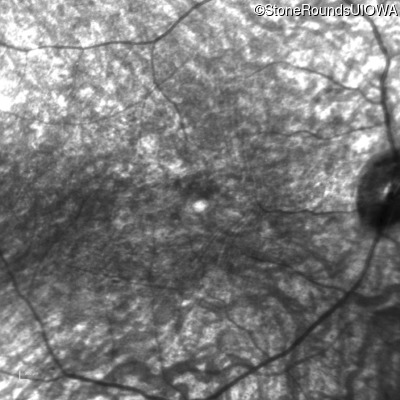

Bardet Biedl Syndrome (IB2)

Age at visit: 25 years

This 25 year old woman has had reduced acuity since age 6 (20/60 OD & 20/100 OS). She had abnormal pigmentation noted in her retina at that time. She had postaxial polydactyl of the left hand and right foot.

Bardet Biedl Syndrome BBS10 Asn222 ins6TGTTGG Lys708 del2gttAA AR